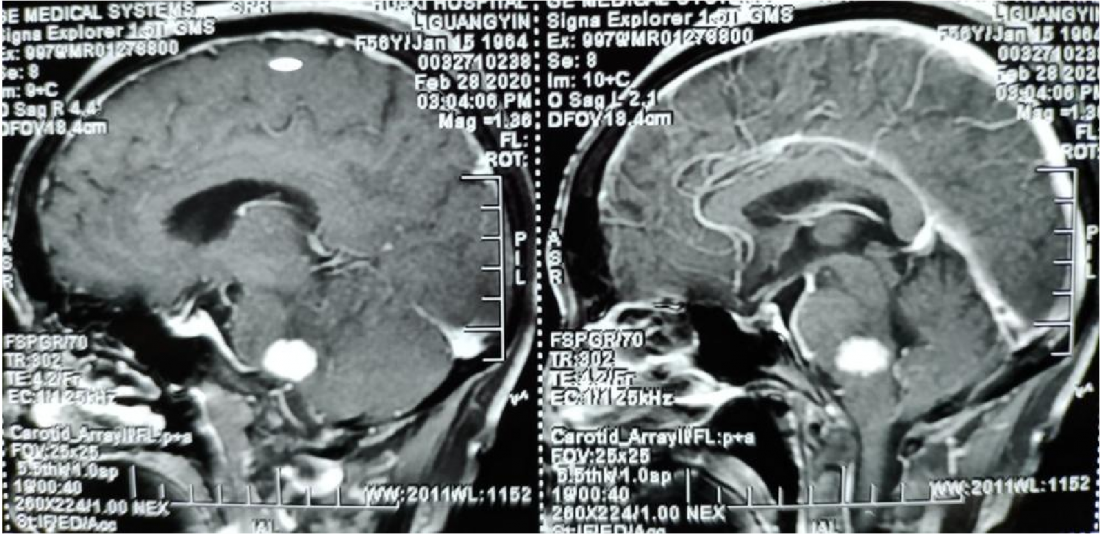

术后MR:

术后患者病理为血管网质细胞瘤。患者恢复良好,行走如常KPS评分90分出院。原先口角歪斜纹明显改善,肢体麻木明显减轻。